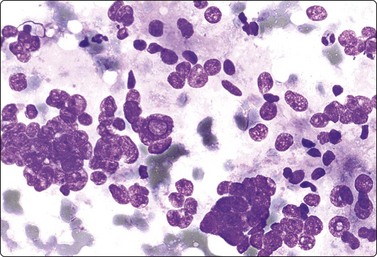

Wilms’ tumor (Figs 12.27 and 12.28)103-105

image

Fig. 12.27 Wilms’ tumor

Biphasic tumor; cohesive tubular structure and undifferentiated mesenchymal cells (MGG, HP).

Fig. 12.28 Wilms’ tumor

Small round cell tumor pattern of undifferentiated blastema (A, MGG; B, Pap, HP).

Criteria for diagnosis

Numerous undifferentiated small cells, single and in tight clusters (blastema),

Small, round or ovoid, hyperchromatic nuclei; multiple small nucleoli,

Scanty cytoplasm,

Epithelial differentiation: rosettes, tubular structures or cords (commonly present),

Mesenchymal differentiation: spindle cells (sometimes present).

Wilms’ tumor (nephroblastoma) is predominantly a tumor of childhood and is dealt with in more detail in Chapter 17. However, it can also occur in adults. Smears are usually dominated by small, undifferentiated malignant cells representing blastema. A specific diagnosis requires in addition evidence of epithelial and mesenchymal differentiation, but this may only be obvious in the better-differentiated tumors. Individual cells generally appear undifferentiated. Epithelial differentiation is suggested by microarchitectural patterns such as rosettes, tubules or cords (Fig. 12.27), which are not always present in smears. Correlation with clinical and radiological findings is important. The diagnosis may be supported by ancillary studies. The results of immunostaining are variable, depending on differentiation. Useful markers are vimentin, LMWCK, EMA and WT1. Heterogeneous cytogenetic abnormalities can be demonstrated in a proportion of tumors.